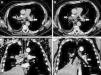

Paciente masculino de 66 años, con diagnóstico de adenocarcinoma de pulmón (estadio iv, con metástasis óseas, en tratamiento con quimioterapia), que desarrolla tromboembolismo pulmonar (TEP), por lo que se indica anticoagulación con heparina, y posterior administración de dicumarínicos. A los 2 meses presenta nuevo episodio de TEP bajo adecuado rango de anticoagulación, por lo que se coloca filtro en vena cava inferior (ELLA Filter®, ELLA-CS sro, República Checa), y continua tratamiento farmacológico con enoxaparina (100mg c/12 horas) más acenocumarol. A los 40 días el paciente presenta disnea súbita y dolor torácico. Se realiza angio-tomografía de tórax, donde se evidencia migración de filtro de vena cava inferior en proyección de la arteria pulmonar izquierda, con trombo adherido, e imagen de trombo pulmonar sub-lobar derecho (fig. 1). Se decide anticoagulación con heparina sódica endovenosa. Angiografía digital evidencia migración de filtro de vena cava inferior a rama lobar inferior izquierda asociado a trombo intra filtro, que se insinúa a bronquio fuente derecho, con fragmento en ramo lobar derecho. Se intenta retirar el filtro, pero es imposible, dado que el mecanismo de cierre y retracción del mismo se encuentra en una rama pulmonar secundaria, en posición distal. El paciente es dado de alta con doble anticoagulación (enoxaparina más acenocumarol). Una radiografía de tórax efectuada a los 2 meses, demuestra la permanencia del filtro en campo pulmonar izquierdo (fig. 2). A 6 meses de seguimiento el paciente permanece vivo, continuando tratamiento quimioterápico, y con hipertensión pulmonar crónica, con presión sistólica pulmonar de 58mm Hg (evaluada por ecocardiograma).